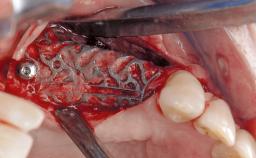

Mauricio Araujo and Flauvia Matarazzo present this straightforward clinical case, demonstrating the potential effect of implant placement depth on the resolution of peri-implant treatment. A 42-year-old systemically healthy female patient, a non-smoker with no history of periodontitis, was treated at the Dental Clinic at the State University of Maringá, Brazil between 2008 and 2009, when she received five implants restored with single crowns at sites 14, 26, 27, 36, and 46. After delivery of the implant-supported prosthetic restorations, the patient was enrolled in the supportive peri-implant therapy (SPiT) maintenance program at the same university.